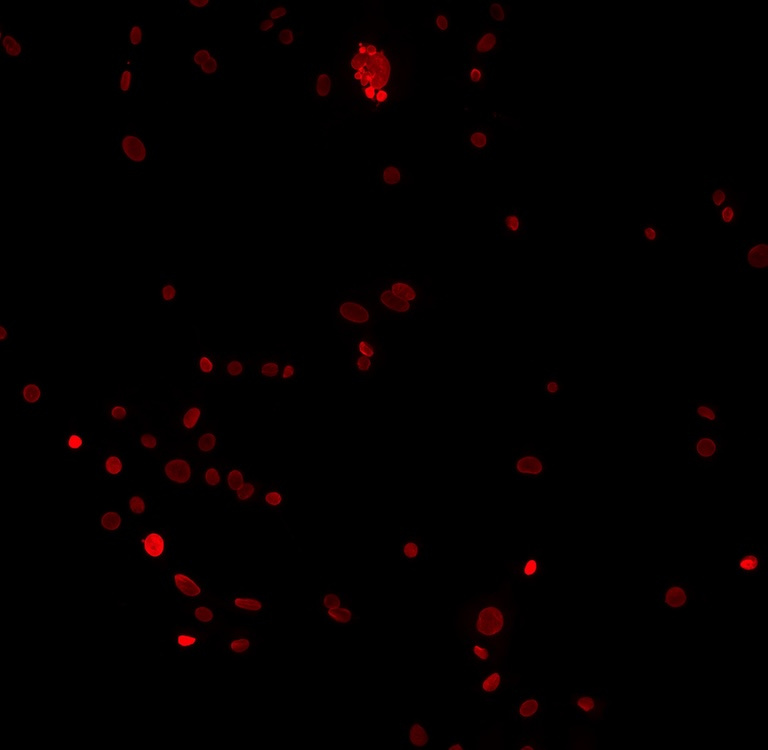

This image shows the heterogeneity of tumor cells that survive chemotherapy treatment. We were trying to see if cytoplasmic DNA or micronuclei were present in tumor cells surviving treatment with DNA-damaging chemotherapies. Indeed, micronuclei were present and some cells were multi-nucleated. Tumor cell size, shape, and nuclear integrity change upon treatment with chemotherapy, yet these cells remain alive.